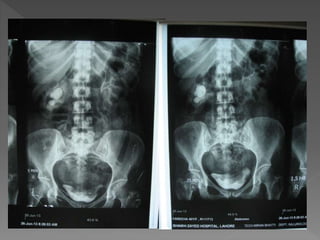

3) 25 mins

X ray films 1)Pre contrast 2) 5 mins 3) 25 mins 4) Post void